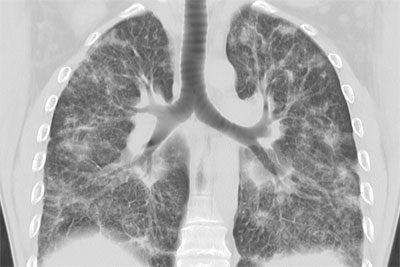

Узлы метастазов имеют ровные края, в редких случаях — волнистые. Когда лёгкие расширяются во время вдоха, форма теней на флюорографии не меняется, нарушения структуры тканей не наблюдается. Множественные метастазы сопровождаются увеличенными лимфоузлами, находящимися в корнях и средостении лёгочного органа.

Поначалу на снимках грудной клетки отчётливо видна деформация лёгочного рисунка. В дальнейшем лимфоузлы увеличиваются, и от них отходят тени в виде прожилок.